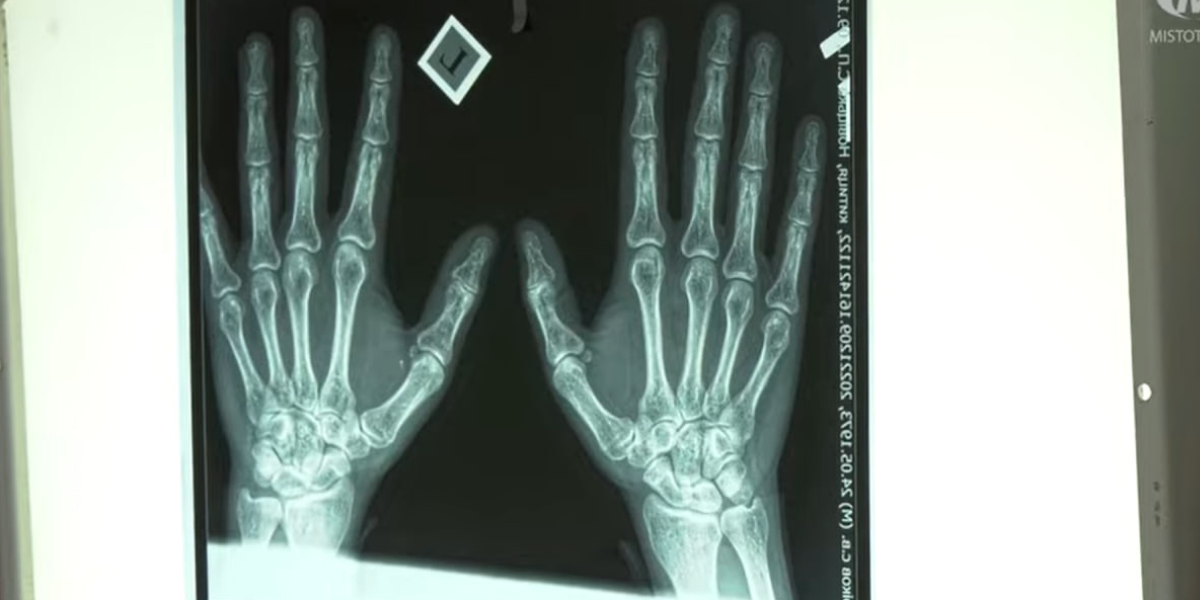

Нещодавно ж міський лікувально-діагностичний центр придбав для поліклінік інноваційне обладнання. Відтепер пацієнти чотирьох поліклінік можуть отримати рентгенівські знімки у “цифрі” замість звичної плівки. Їх не потрібно проявляти і сушити, як це було раніше. Бо плівку замінить електронна касета.

Рентген-апарат у 1 поліклініці працює вже більше 20 років. Відтепер він матиме сучасний рентгенівський детектор. Знімок надходитиме на комп’ютер всього за декілька секунд. За необхідності висновки та обстеження можуть надіслати на електронку лікаря та пацієнта. А щоб роздрукувати результат придбали спеціальний принтер сухого друку.

Таке цифрове обладнання лікувально-діагностичний центр закупив для 4-х міських поліклінік. Вартість одного комплекту обійшлася в 1,1 мільйона гривень. Сумарно витратили 4,4 мільйони гривень.

— Це дає змогу отримати більш якісні результати обстеження, більш якісні рентгенівські знімки. Крім того, проведені торги на придбання нового рентген-апарату в 5-ту поліклініку. Але поки що ми його ще не отримали, — повідомив начальник управління охорони здоров’я Борис Ткач.